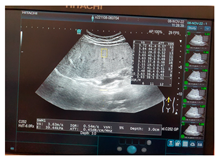

| Ultrasound | ![]() | ![]() | ![]() |